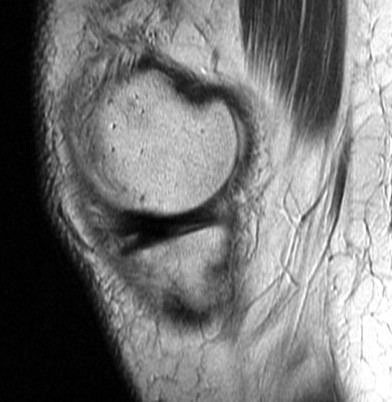

Figure 2 for case Unstable flap tear medial meniscus

Figure 2

With a displaced flap into the coronary recess. No sign of patellar dislocation. PD fat sat shows the inflammatory change that often accompanies and unstable tear. Displacement of meniscal tissue=instability.

Unstable flap tear medial meniscus